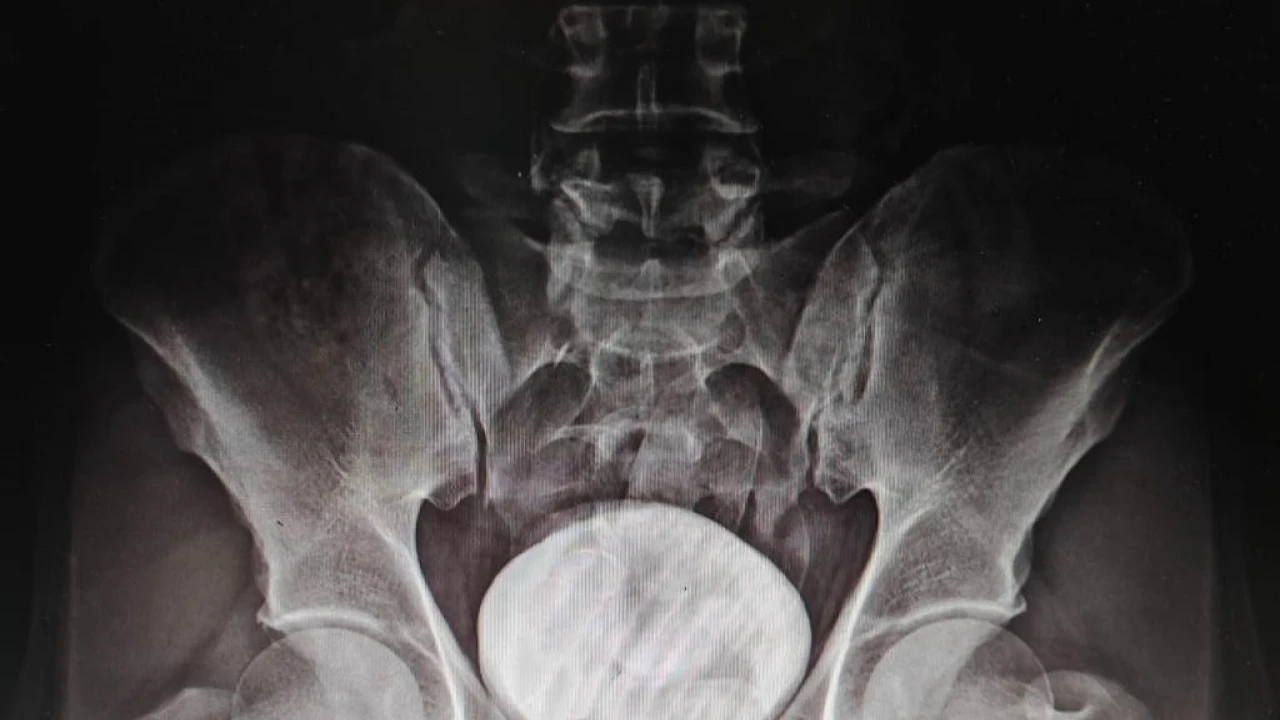

Polis yaptığı üst aramasında bir şey bulamayınca şüpheliyi Kars Harakani Devlet Hastanesine götürdü. Burada çekilen röntgen sonucu Mohammad Zadeh Tazehkand’ın mide ve bağırsaklarında kapsüller içerisinde 7 parça halinde 258,53 gram metamfetamin maddesi tespit etti.